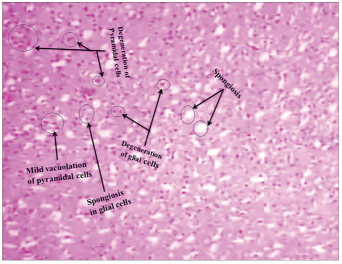

In control rat brain section, normal glial cells and pyramidal cells were noticed as shown in Figure 4. But in ACR administered (50 mg/300 ml water up to 27 days in alternative days), rat brain that histological variations were observed like degeneration of pyramidal cells, degeneration of glial cells, mild vacuolation of pyramidal cells, spongiosis in glia cells and spongiosis, on 13th day post-ingestion as shown in Figure 5, and necrosis and pyknosis, necrosis of neurons and neurophagia, focal gliosis and demyelination of nerve fibers, on 27th day post-ingestion as shown in Figure 6.

Figure 5: Rat cerebellum section shows that degeneration of pyramidal cells, degeneration of glial cells, mild vacuolation of pyramidal cells, spongiosis in glial cells, and spongiosis on 13th day post-ingestion of acrylamide (H and E stain) (×10)

In the present study, ACR-administered rat brain histopathological changes such as degeneration of pyramidal cells, degeneration of glial cells, mild vacuolation of pyramidal cells, spongiosis in glia cells, and spongiosis were observed by 13th day, as shown in Figure 5 as well as necrosis and pyknosis, necrosis of neurons and neurophagia, focal gliosis, and demyelination of nerve fibers were observed by 27th day, as shown in Figure 6 when compared to control, i.e., as shown in Figure 4. Cells such as astrocytes, microglia, neurons, and oligodendrocytes of central nervous system have various functions [85]. Communication disturbances between the brain cells lead to the development of neurodegeneration disorders as well as initiation and progression of neurotoxicity that induced by xenobiotics [86,87]. Jangir et al. [88] has notice the histopathological variations like neuronal degeneration, edema and congestion in ACR treated rat brain. Sub-acute exposure of ACR leads to the degeneration of cerebral cortex and cerebellum in rats [89]. Brain possesses low levels of antioxidant enzymes so that the brain is susceptible to toxic agents. As shown in Figures 5 and 6, in the present study, we observed the degenerative changes in ACR-administered rat brain as stated by Cerbai et al. [86], Li et al. [87], Jangir et al. [88] and Zhao et al. [89].